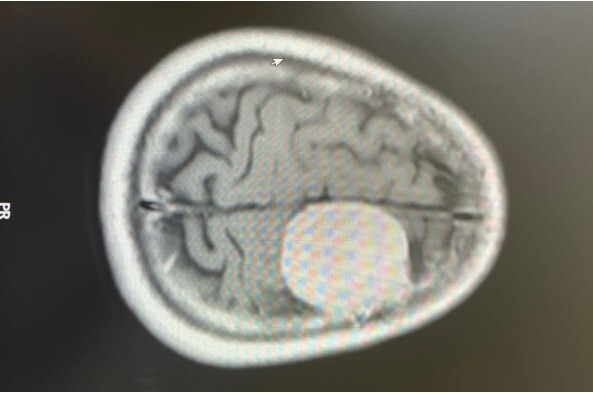

Trước khi được chẩn đoán dương tính với Adenovirus, bệnh nhi đã xuất hiện triệu chứng co giật kín đáo, không rõ cơn giật điển hình hay tím tái. Tuy nhiên, khi được chọc dịch não tủy xét nghiệm theo dõi viêm não/màng não, kết quả thu được lại hoàn toàn bình thường, phù hợp với lứa tuổi.

Sau đó vài ngày, bệnh nhi được xét nghiệm Adenovirus bằng phương pháp Realtime PCR tại Bệnh viện Nhi Trung ương mới cho kết quả dương tính, các triệu chứng co giật rõ rệt hơn, các cơn co giật xuất hiện với tần suất nhiều hơn và kéo dài (trong khoảng 10 phút).

Sau co giật, bệnh nhi không tỉnh lại, giảm ý thức và bắt đầu có tình trạng yếu liệt chân tay 2 bên. Bệnh nhi được điều trị an thần, thở máy kết hợp với kháng sinh liều cao, điều trị tình trạng viêm não, màng não, chống phù não, tăng áp lực nội sọ.

Qua một thời gian điều trị, tình trạng của bệnh nhi đã ổn định hơn, tình trạng sốt cao đã được cải thiện. Tuy nhiên, di chứng của viêm màng não sau nhiễm Adenovirus khiến bé bị liệt mềm toàn thân, cần rất nhiều thời gian để cải thiện. Hiện, bệnh nhi đang tiếp tục được điều trị tại Bệnh viện Sản Nhi tỉnh Phú Thọ với phác đồ bằng an thần thở máy, truyền albumin, truyền máu kết hợp sử dụng các thuốc kháng sinh.